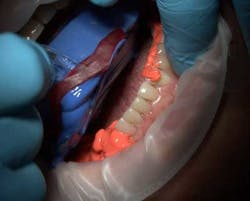

Fig. 2B: Customizing upper tray for open tray implant transfer and precise palatal positioning for implant screws.Isolate and dry the area that is going to be impressed (Fig. 3). While extruding the wash material around the preparation, it’s important to keep the tip buried to prevent voids or air pockets. When extruded, the thixotropic properties of the wash material allows the material to stay on the preparation and not flow all over the patient’s mouth (Fig. 4).

Fig. 4: Extruding Virtual XD onto the preparation and note thumb support and guidance for controlled rapid delivery.Insert the tray far enough into the mouth so you can seat it straight up or down over the teeth (Figs. 5 and 6). When the tray material is placed, the material starts to penetrate and flow deep into the sulcus, capturing the necessary detail. Hold the tray in place for the minimum set time, which can range from 2-and-a-half minutes for fast set to 4-and-a-half minutes for regular set with this material. After the set time, check the material to verify the tray material has set and remove the tray very slowly, not from the handle, but rather first breaking posterior seal. This is especially important with double cord technique to avoid marginal tears from possible cord attaching to material.